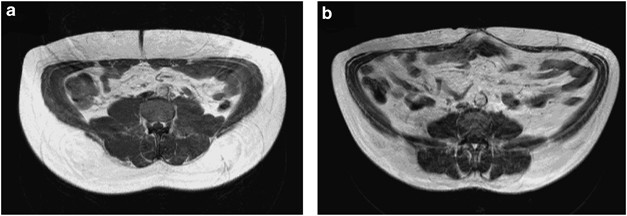

A single-slice MRI image for two subjects of the same gender with near-identical ViScan visceral fat scores (a=19.5; b=20 arbitrary units) but differing IAAT as assessed by MRI (a=3.2; b=6.3 l). Interestingly, when abdominal subcutaneous fat was considered (a=13.6; b=9.2 l), these two subjects showed similar overall levels of total abdominal adiposity (a=16.8; b=15.5 l).